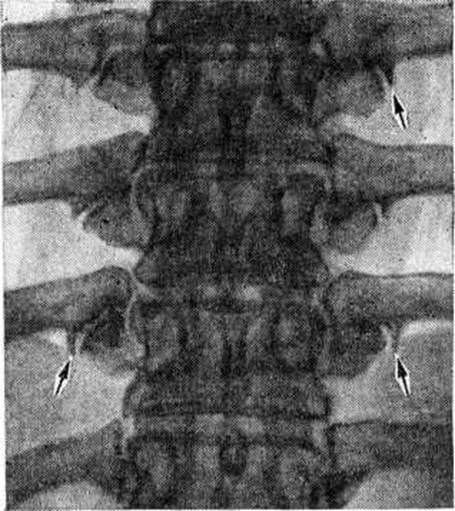

Диагноз Спондилоартроз ставят главным образом на основании клиники и данных рентгенологического исследования. На рентгенограммах определяется сужение суставных щелей, субхондральный остеосклероз (смотри полный свод знаний), краевые костные разрастания (рисунок), продолжающие суставные поверхности, удлинение и деформация суставных отростков.

Поскольку стандартная (в прямой и боковой проекциях) рентгенография не создает оптимальных условий для суждения о состоянии дугоотростчатых суставов, обычно применяют специальные прицельные снимки при повороте пациента вдоль продольной оси на 30—45°. Как дополнительные методики могут быть применены томография и рентгеновские снимки в положении максимального сгибания и разгибания позвоночника.